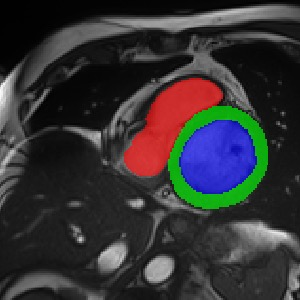

Transformers, the default model of choices in natural language processing, have drawn scant attention from the medical imaging community. Given the ability to exploit long-term dependencies, transformers are promising to help atypical convolutional neural networks (convnets) to overcome its inherent shortcomings of spatial inductive bias. However, most of recently proposed transformer-based segmentation approaches simply treated transformers as assisted modules to help encode global context into convolutional representations without investigating how to optimally combine self-attention (i.e., the core of transformers) with convolution. To address this issue, in this paper, we introduce nnFormer (i.e., Not-aNother transFormer), a powerful segmentation model with an interleaved architecture based on empirical combination of self-attention and convolution. In practice, nnFormer learns volumetric representations from 3D local volumes. Compared to the naive voxel-level self-attention implementation, such volume-based operations help to reduce the computational complexity by approximate 98% and 99.5% on Synapse and ACDC datasets, respectively. In comparison to prior-art network configurations, nnFormer achieves tremendous improvements over previous transformer-based methods on two commonly used datasets Synapse and ACDC. For instance, nnFormer outperforms Swin-UNet by over 7 percents on Synapse. Even when compared to nnUNet, currently the best performing fully-convolutional medical segmentation network, nnFormer still provides slightly better performance on Synapse and ACDC.